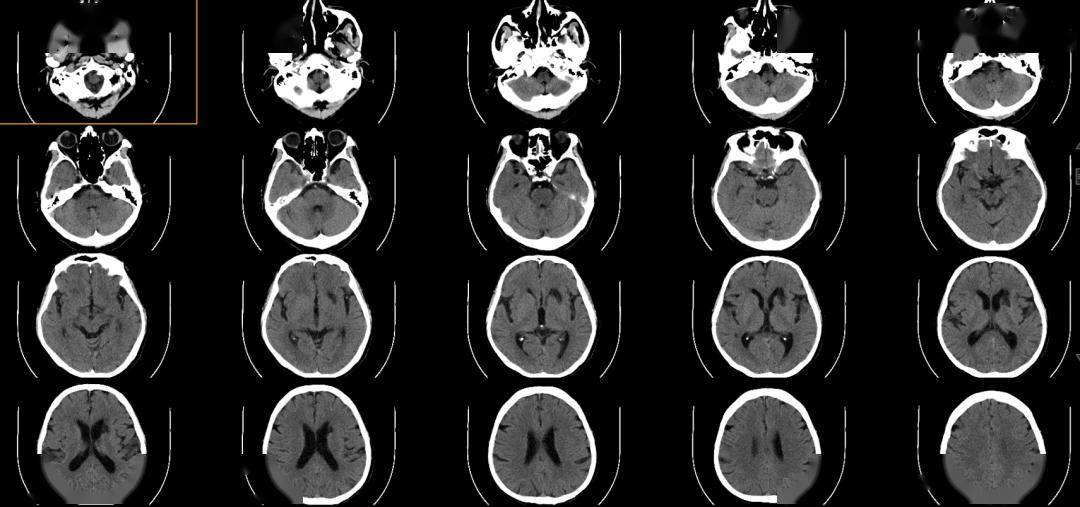

术前影像

术前正位DSA

术前侧位DSA

术前CT

初步诊断:右侧大脑中动脉M1动脉瘤

侧别、位置:右侧

动脉瘤的形态:囊性

动脉瘤大小:长15.0mm、宽16.6mm、高15.1mm

动脉瘤颈宽度:12.0mm

载瘤动脉直径:远端3.8mm,近端4.6mm

术后CT